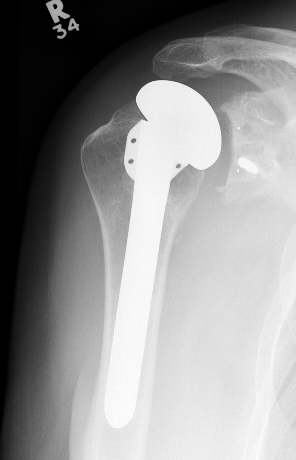

TSR Periprosthetic FractureTSR Periprosthetic Fracture

aTSA fracture 1aTSA fracture 2revTSA following fracturerevTSA for fracture